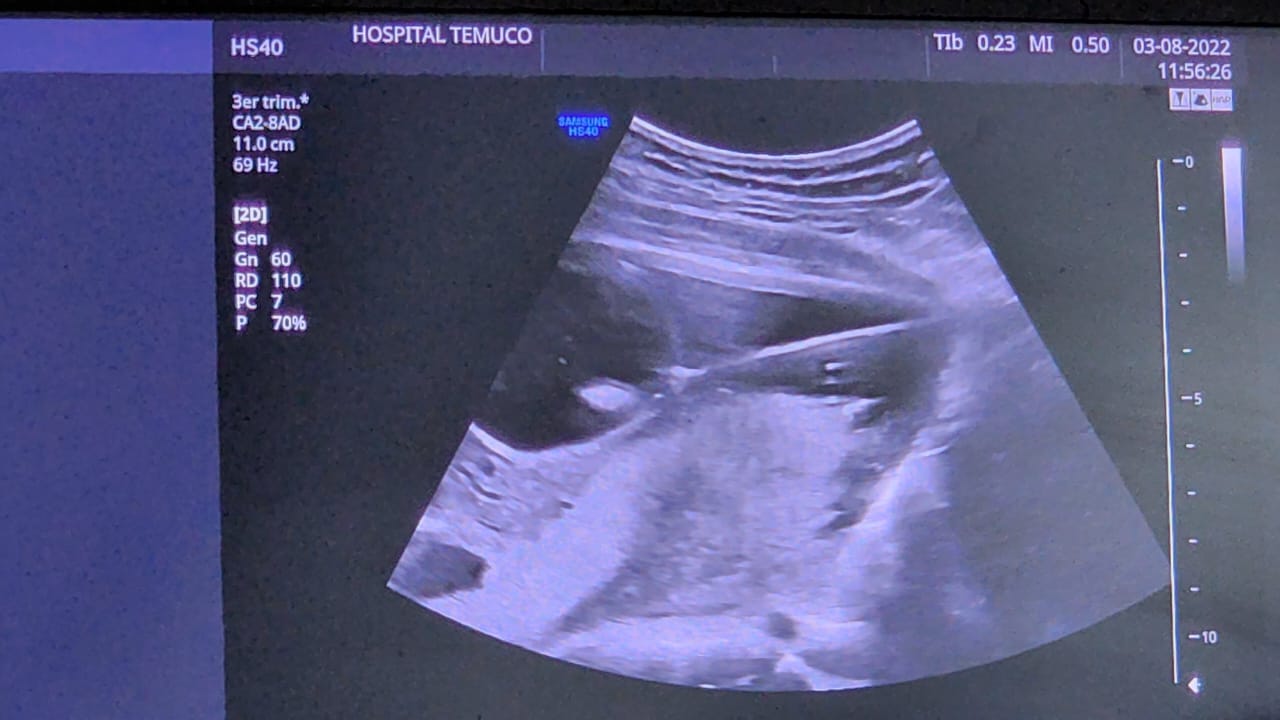

Un importante hito desarrolló el equipo de Alto Riesgo Obstétrico del Hospital Hernán Henríquez Aravena, al intervenir, dentro del útero de su madre, a un bebé de 19 semanas de gestación, con obstrucción en la vejiga, que hacía poco viable llevar a término el embarazo.

La intervención realizada consistió en “poner un drenaje en la vejiga, para que el pipí que el bebé no podía evacuar de manera natural, saliera hacia afuera; algo muy similar a lo que se hace en adultos con obstrucciones que se les pone un drenaje desde la vejiga hacia afuera, con la diferencia que esta vez, se hizo hacia el útero de la mamá, lo que permite que el feto pueda hacer pipí y seguir desarrollándose”.